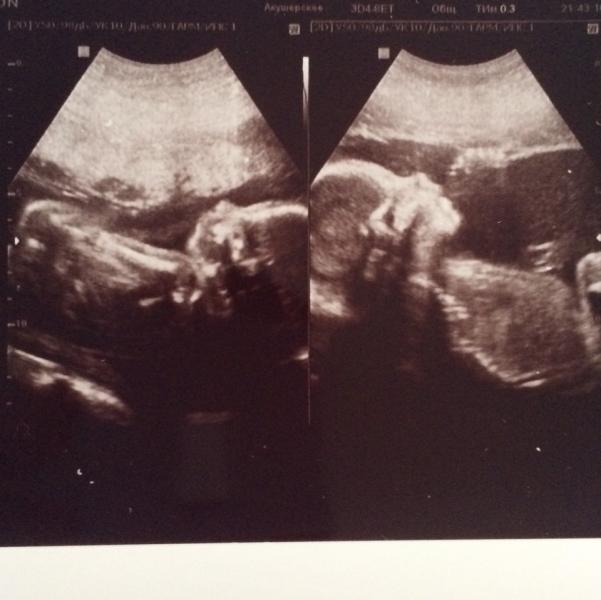

Сегодня сходила на УЗИ к Макаровой в Краевой роддом . Нужно было сердечко у сыночка ещё раз глянуть ( в прошлый раз лёг неудачно ) . Ещё раз подтвердила , что мальчик и девочка 🤗🤗☺️. Сыночек на попе сидит , а доча головой вниз . Скромная девочка , всегда лицо ручками закрывала 🙈🙈🙈. Долго сфоткать пытались . P.s. Почитав про долгие очереди , я приехала к 8 утра , была третьей. Врач кстати тоже приём в 8 начала . Зашла я в 9 . В целом всем довольна , всё рассказала , показала . За приём отдала 50...